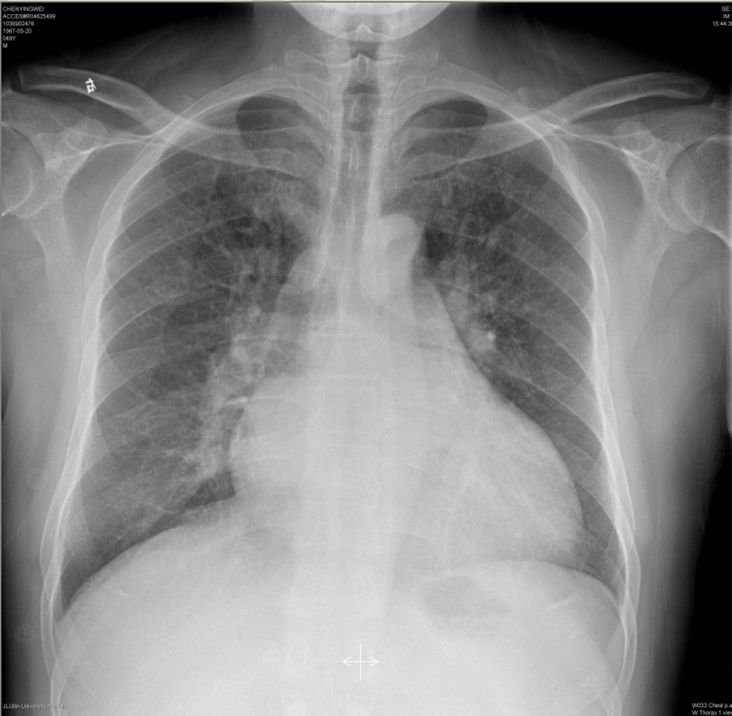

(胸片:心影增大)